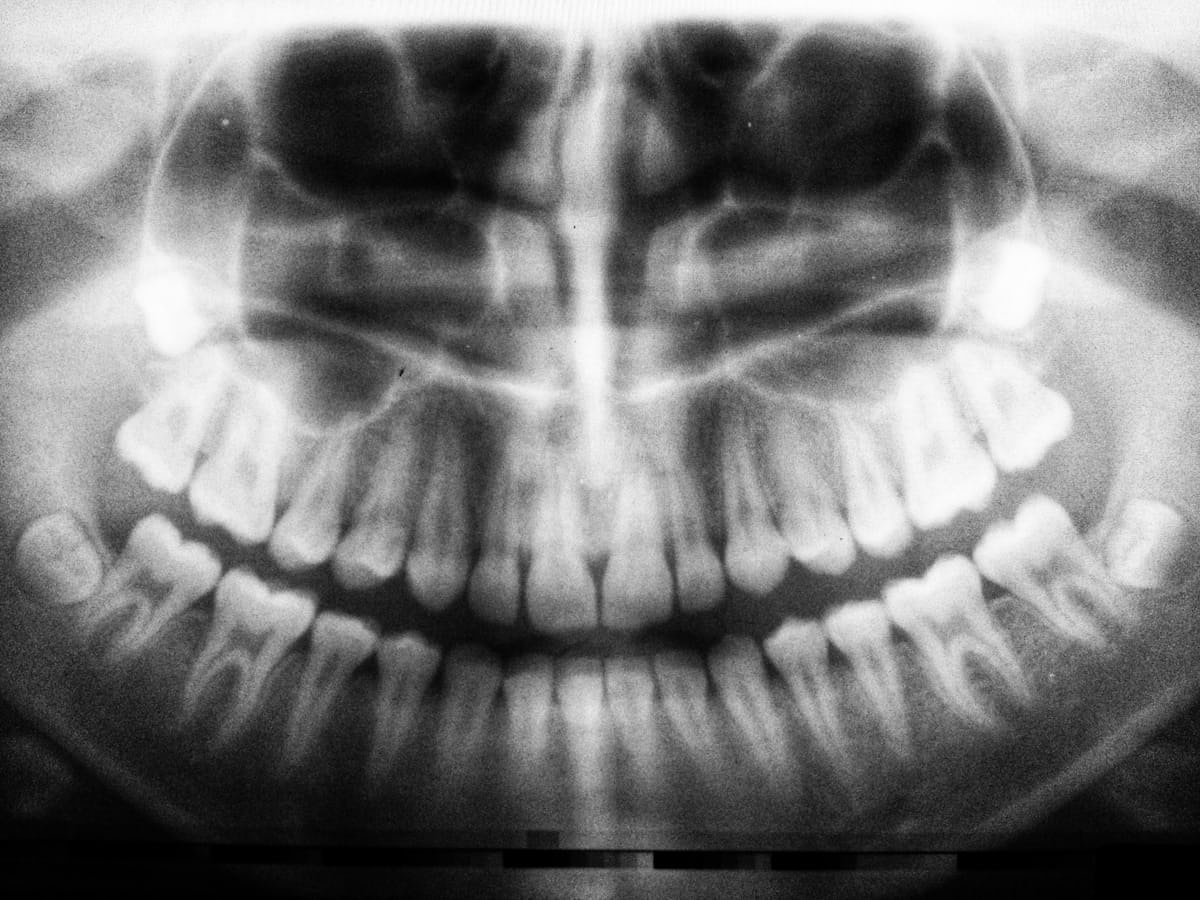

Prosthodontics offers solutions like crowns, bridges, and dentures to restore your smile and functionality.